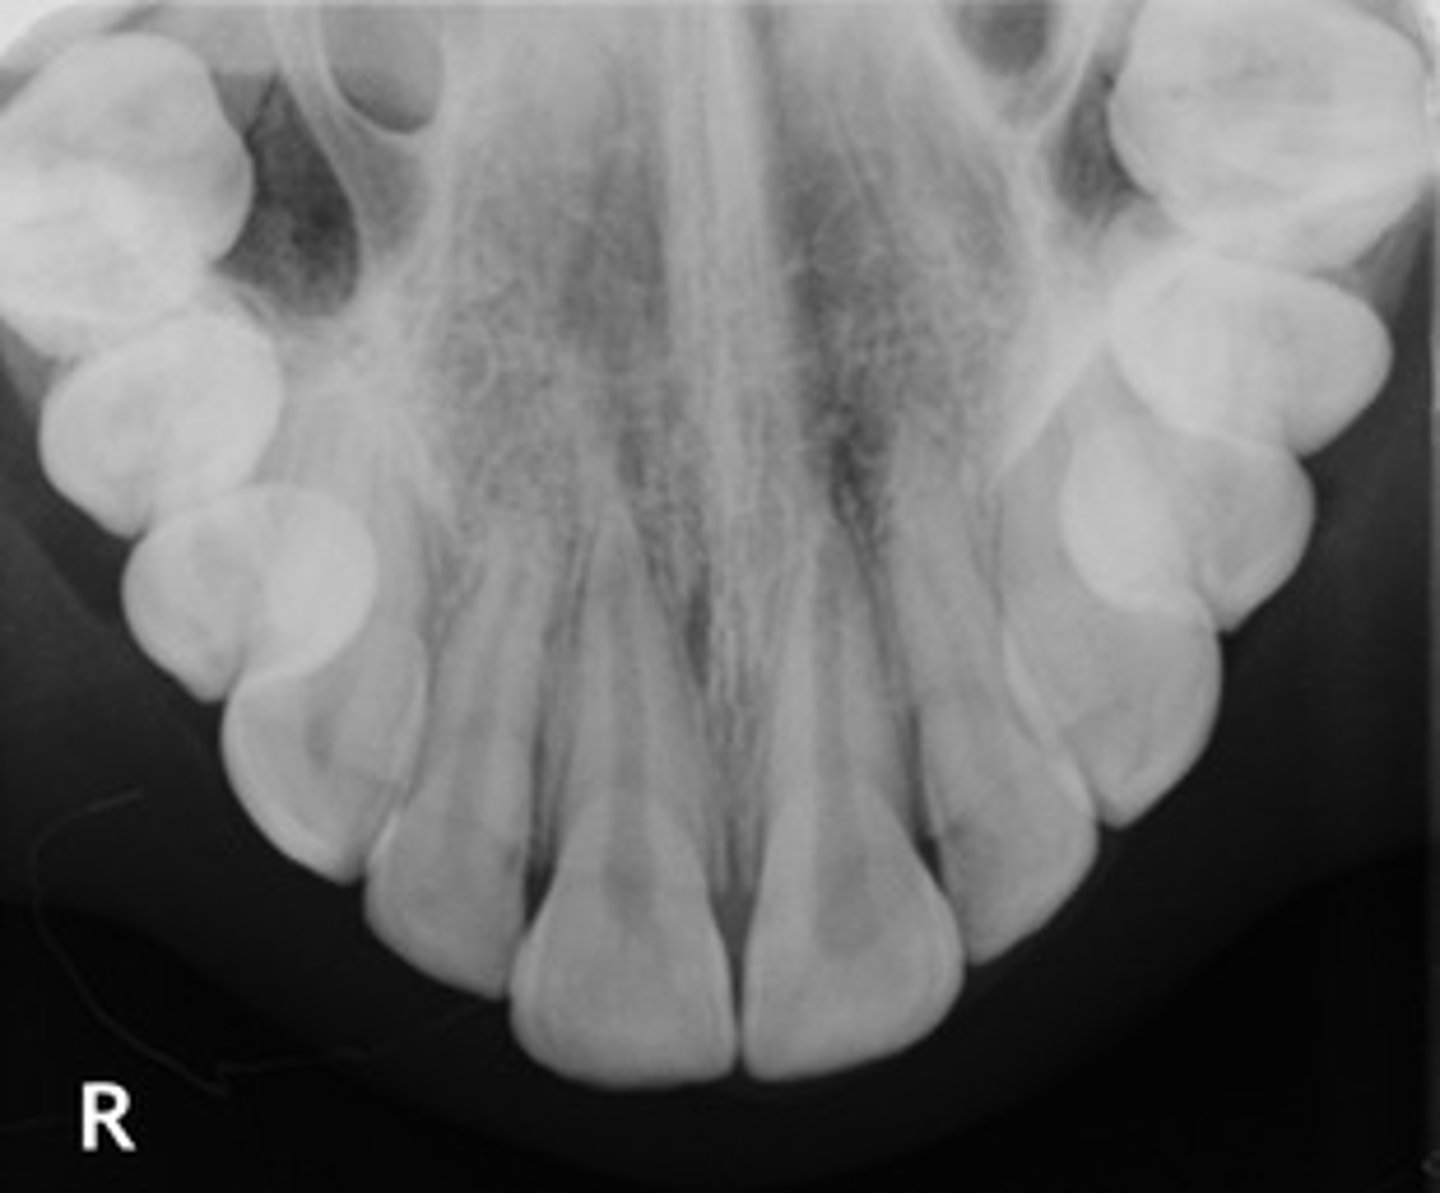

Occlusal radiograph

image that shows large areas of the maxilla or mandible

Occlusal radiograph purpose:

help track the development & placement of a section or entire arch of teeth in the upper or lower jaw